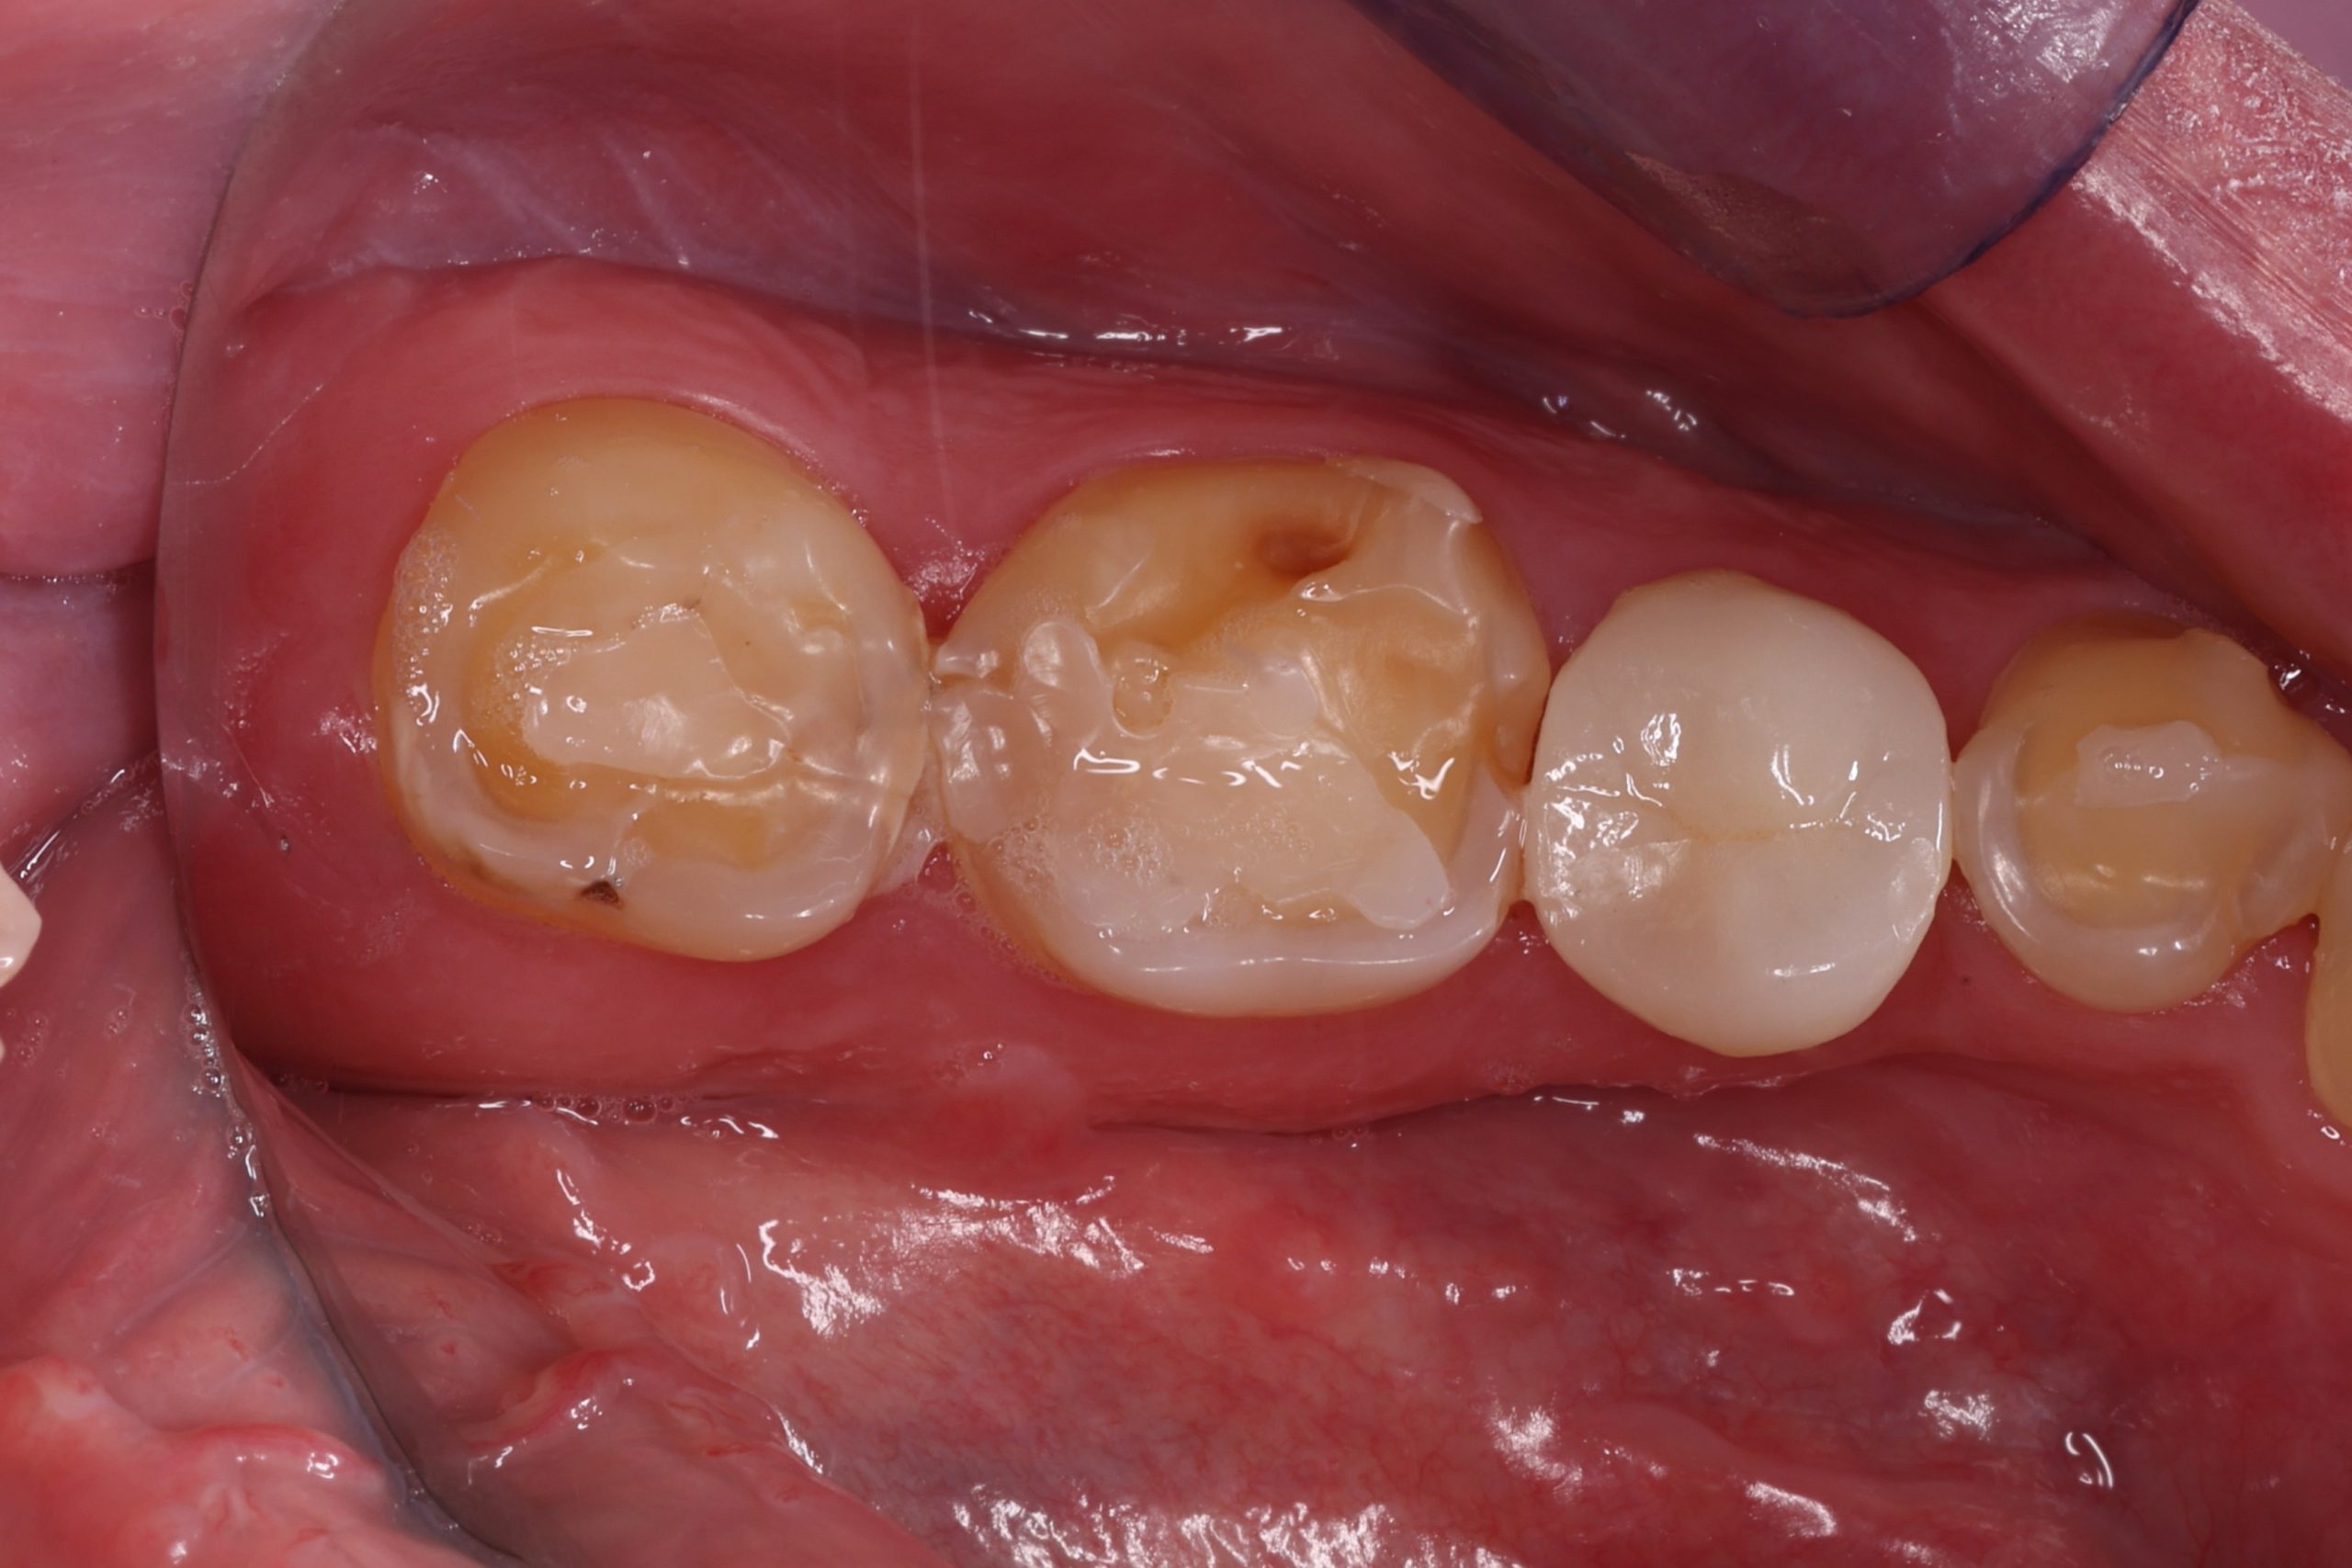

1. Preparation of the Tooth

We remove weakened or decayed tissue and clean the area thoroughly. The goal is to preserve as much healthy structure as possible.

3. Layering the Composite Resin

The tooth-coloured resin is applied in thin layers and shaped carefully to match natural anatomy. For front-tooth work, we may combine several shades for a lifelike result.

• replacing old metal fillings with a tooth-coloured option

For extensive damage or deeper cracks, we may discuss ceramic inlays, onlays, or crowns. Your dentist will recommend the most stable option based on diagnosis, not trends.